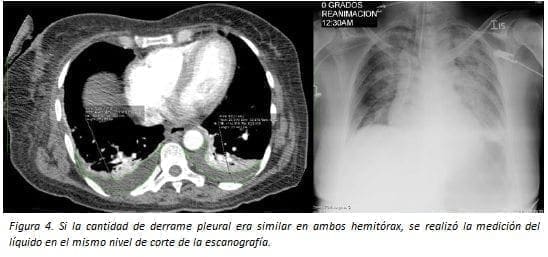

La cantidad depende del área en cm2 obtenida en escanografía de tórax en corte axial en el sitio donde era más abundante. Esta medida del área fue convertida en mililitros utilizando la fórmula ml = (cm2 x 100) x 0,1.

A su vez fue determinado como escaso si es <75 ml, moderado entre 75 y 350 ml y abundante si es mayor de 350 ml (figuras 1-5).